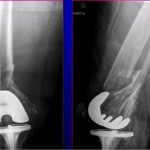

Courtesy: Prof Nabil Ebraheim, University of Toledo, Ohio, USA

X-ray Findings

- Often difficult to interpret

Reason

- Epiphysis may not be ossified

Key Clue

- Ossification center:

- Not aligned with femoral shaft

MRI (Best Investigation)

- Confirms diagnosis when X-ray is inconclusive